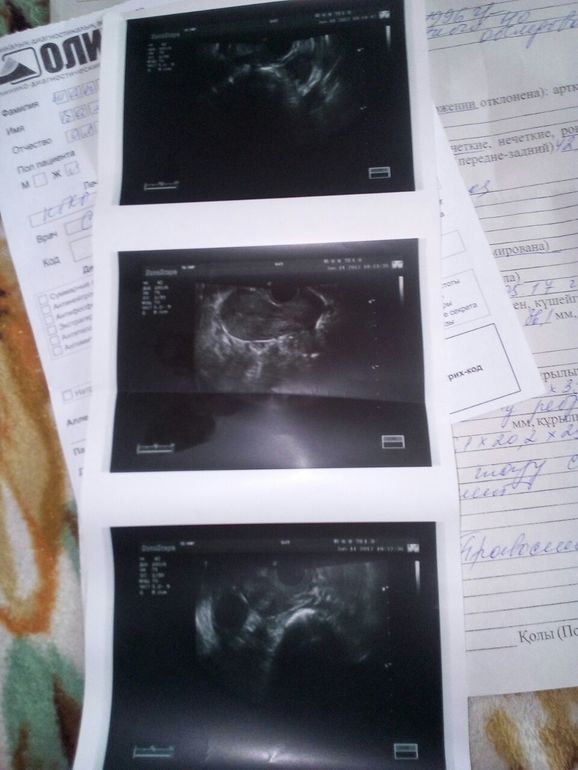

Судя по заключению УЗИ у вас хр воспалительный процесс. И сначала желательно пролечиться . Назначения у вас есть.

Если правильно разобрала фоллик 24 мм, при таких размерах обычно лопается, значит О будет сегодня/завтра!